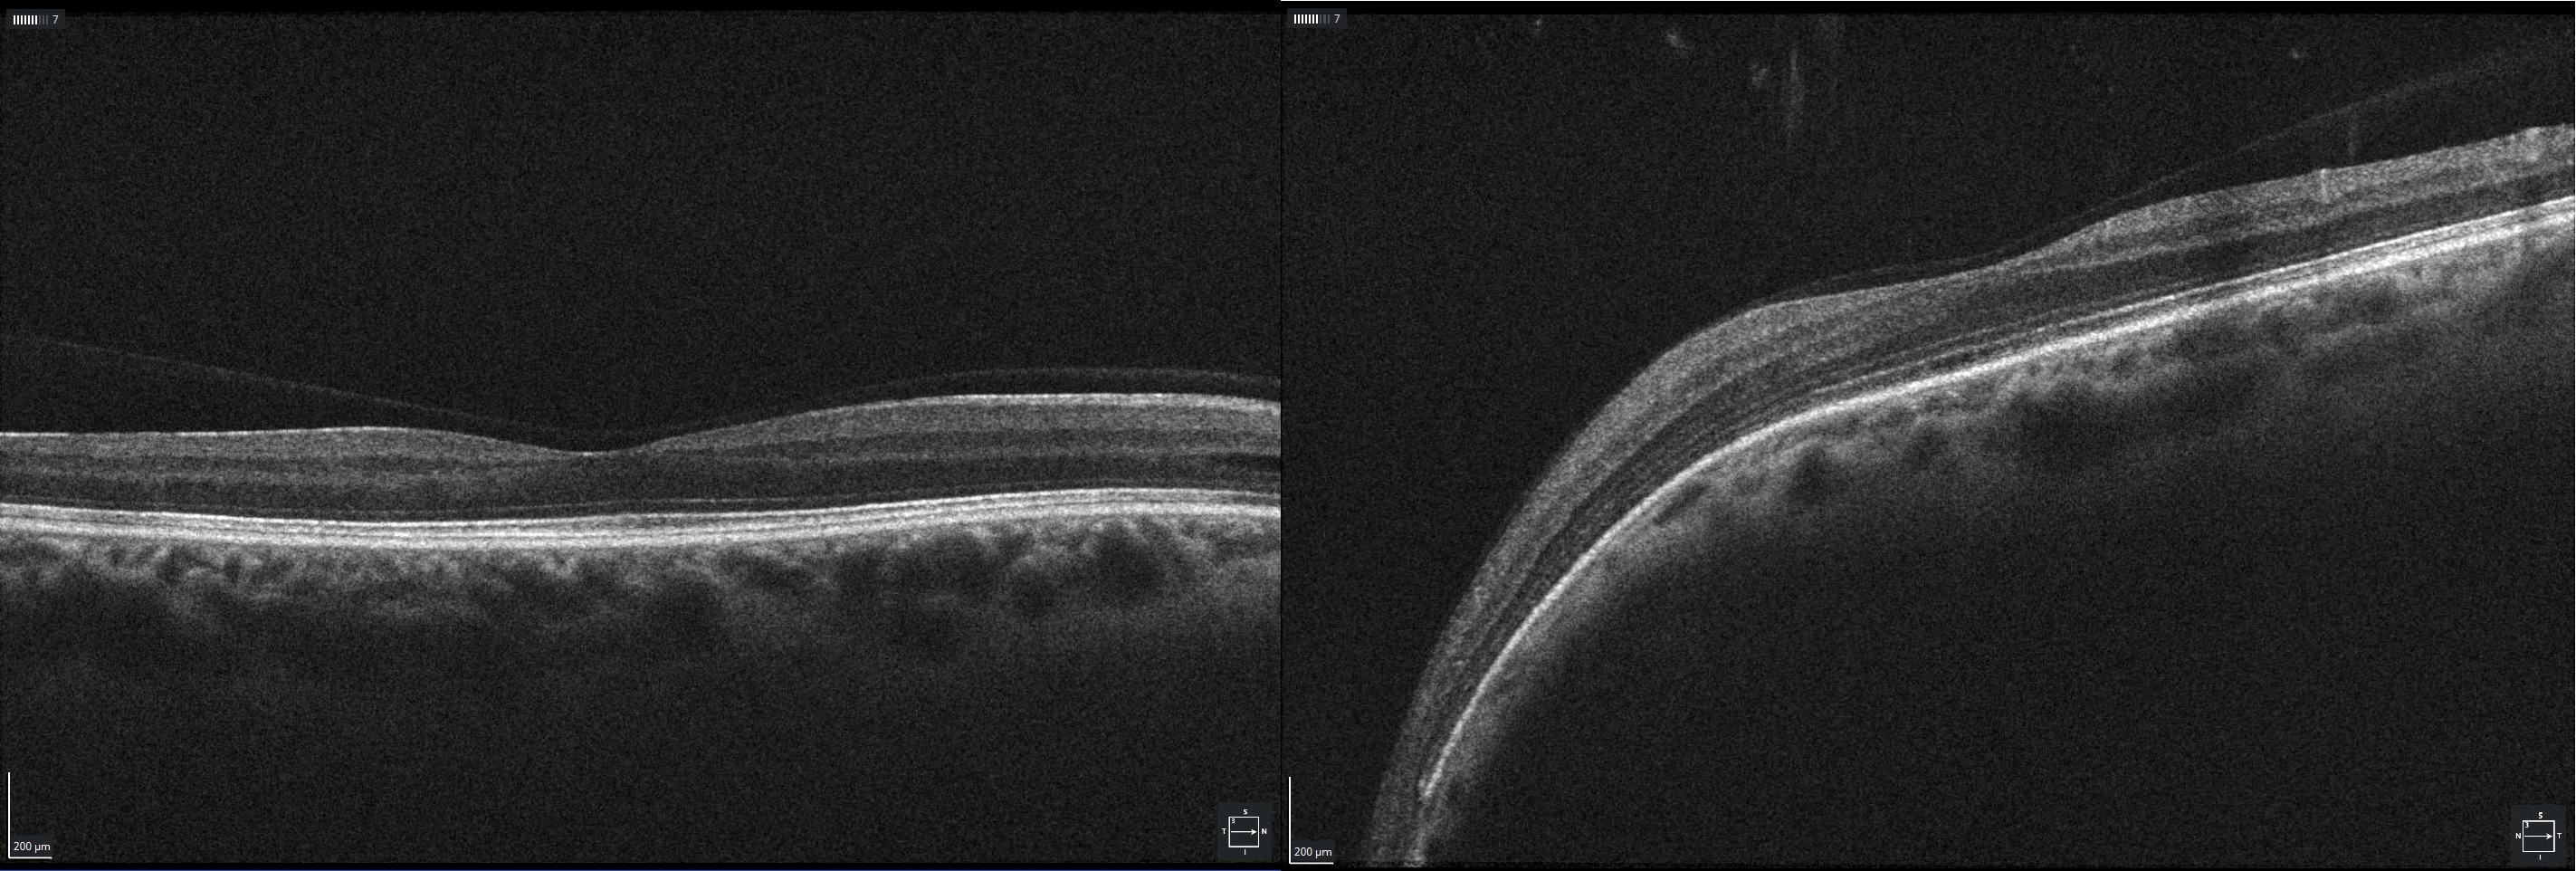

Renal coloboma syndrome or papillorenal syndrome is an autosomal dominant genetic disorder characterized by congenital renal and ocular disorders associated with variations in the PAX2 gene. In this case report, a 46-year-old gentleman presented for ocular examination in the setting of systemic hypertension. Past medical history included a kidney transplant due to renal failure. Fundus examination revealed bilateral optic nerve abnormalities with a large central excavation, with numerous vessels radiating from the periphery of the optic disc, consistent with the Morning Glory anomaly. Optical coherence tomography (OCT) disclosed substantial thinning of retinal nerve fiber layer. Genetic studies revealed the heterozygous variant c.398delC in the 3’ exon of PAX2 gene not previously described in the peer-reviewed medical literature (searched using MEDLINE and cross-referenced literature).

- Figure 2. The Optical Coherence Tomography (OCT) proved a significant thinning of the retinal nerve fiber layer on both eye papillae.